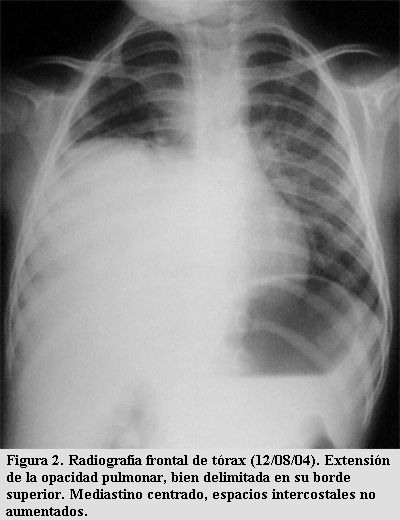

12 de agosto 2004. Consulta nuevamente por fatiga, se realiza nueva radiografía de tórax (figura 2), en la cual se observa extensa opacidad del hemitórax derecho, que es interpretada por el médico pediatra como neumonía extensa, con foco no resuelto. Se medica con vancomicina.

Preescolar de 3 años de edad, producto de segunda gestación, embarazo bien controlado y tolerado, ecografías prenatales normales. Sin antecedentes personales patológicos. Inmunizado. Buen crecimiento y desarrollo. El 27 de julio de 2004 consulta en centro de asistencia médica del interior del país, siendo ingresado por el médico pediatra con el diagnóstico clínico - radiográfico de neumonía de comienzo agudo, extensa, con compromiso pleural (figura 1). Se inicia tratamiento médico, recibiendo antibióticos de primera línea, con buena evolución clínica. Se otorga el alta.